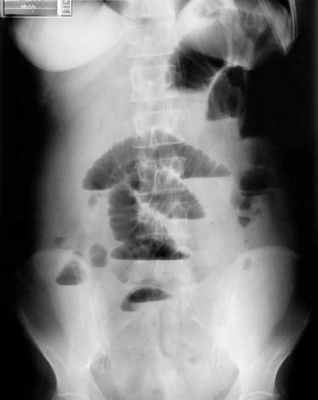

Рентгенологическое исследование является основным специальным методом диагностики ОКН. При этом выявляются следующие признаки:

- Чаша Клойбера – горизонтальный уровень жидкости с куполообразным просветлением над ним, что имеет вид перевернутой вверх дном чаши. При странгуляционной непроходимости могут проявляться уже через 1 час, а при обтурационной непроходимости — через 3-5 часов с момента заболевания. Количество чаш бывает различным, иногда они могут наслаиваться одна на другую в виде ступенчатой лестницы.

- Кишечные аркады. Получаются, когда тонкая кишка оказывается раздутой газами, при этом в нижних коленах аркад видны горизонтальные уровни жидкости.

- Симптом перистости (поперечная исчерченность в форме растянутой пружины) встречается при высокой кишечной непроходимости и связан с растяжением тощей кишки, имеющей высокие циркулярные складки слизистой. Контрастное исследование желудочно-кишечного тракта применяется при затруднениях в диагностике кишечной непроходимости. Больному дают выпить 50 мл бариевой взвеси и проводят динамическое исследование пассажа бария. Задержка его до 4-6 часов и более дает основание заподозрить нарушение двигательной функции кишечника.

Рентгенологическая диагностика острой кишечной непроходимости. Уже через 6 ч от начала заболевания имеются рентгенологические признаки кишечной непроходимости.

1. Рентгенологическое обследование является основным специальным методом диагностики ОКН. Обзорная рентгенография брюшной полости должна проводиться при малейшем подозрении на ОКН. При этом выявляется ряд признаков. В норме газ имеется в ободочной кишке. Появление газа в тонкой кишке указывает на непроходимость. Характер скопления газа в просвете кишечника различается при разных вариантах КН (рис. 1). Рисунок 1. Схема скопления газа в просвете кишечника при разных вариантах КН. а - высокая тонкокишечная непроходимость. Возможно наличие единичных горизонтальных уровней жидкости и газа. Наличие газа в толстой кишке не характерно Рисунок 1. Схема скопления газа в просвете кишечника при разных вариантах КН. б - низкая тонкокишечная непроходимость. Обычно видны множественные горизонтальные уровни жидкости и газа (чаши Клойберга). Наличие газа в толстой кишке не характерно Рисунок 1. Схема скопления газа в просвете кишечника при разных вариантах КН. в - странгуляционная кишечная непроходимость. Могут быть как единичные, так и множественные горизонтальные уровни жидкости и газа. Наличие газа в толстой кишке не характерно. Обычно по снимкам удается определить, петли какой кишки - тонкой, толстой или обеих - растянуты газом. При наличии газа в тонкой кишке хорошо видны спиралевидные складки слизистой оболочки (Керкринговы складки), занимающие весь поперечник кишки.

В тощей кишке они имеют вид круговой ребристости, напоминающей «скелет селедки» (симптом Кейcи), в подвздошной кишке - более редкие, прямые и толстые. При скоплении газа в толстой кишке видны гаустры, которые занимают лишь часть поперечника кишки [7, 9-12].

В более ранних стадиях КН рентгенологически может определяться скопление газа (без уровня жидкости) в петле кишки соответственно определяемому клинически симптому Валя (симптом Гинтце). На соответствие растянутой и напряженной петле кишки зоны скопления газа в виде арки указывает симптом Штирлина.

При механической тонкокишечной непроходимости в толстой кишке газа немного или нет. При толстокишечной непроходимости и сохранной функции илеоцекального клапана отмечают значительное вздутие толстой кишки, в тонкой кишке газ может отсутствовать. Недостаточность илеоцекального клапана приводит к растяжению как тонкой, так и толстой кишки.

На рентгенограммах, полученных в положении стоя или лежа на боку, обычно видны горизонтальные уровни жидкости и газа (рис. 2). Рисунок 2. Обзорная рентгенограмма брюшной полости. Видны чаши Клойбера, уровни жидкости. Заполненные газом кишечные петли имеют вид опрокинутых чаш (чаши Клойбера). Они появляются при странгуляции через 1-2 ч после начала заболевания, при обтурации - через 3-5 ч. По размерам чаш Клойбера, их форме и локализации можно судить об уровне непроходимости.

При тонкокишечной непроходимости чаши Клойбера небольших размеров, ширина горизонтального уровня жидкости больше, чем высота столба газа над ним. Обычно наблюдается большое количество горизонтальных уровней с изменением их расположения в течение времени и перемещением жидкости из одной петли в другую. Горизонтальные уровни жидкости ровные. На фоне газа хорошо видны складки слизистой оболочки (складки Керкринга), принимающие форму растянутой спирали.

При непроходимости тощей кишки горизонтальные уровни жидкости локализуются в левом подреберье и эпигастральной области. При непроходимости в терминальном отделе подвздошной кишки уровни жидкости расположены в области мезогастрия.

При тонкокишечной непроходимости, кроме чаш Клойбера, на рентгенограммах видны растянутые газом кишечные петли, принимающие форму «аркад» или «органных труб», похожих на перевернутые буквы J и U.

При толстокишечной непроходимости горизонтальные уровни жидкости расположены по периферии брюшной полости, в боковых отделах живота, и их меньше, чем при тонкокишечной непроходимости. Высота чаш Клойбера преобладает над шириной. На фоне газа видны полулунные складки слизистой оболочки («гаустры»). Уровни жидкости не имеют ровной поверхности («зеркала»), что обусловлено наличием в толстой кишке плотных кусочков кала, плавающих на поверхности жидкого кишечного содержимого.

При динамической паралитической непроходимости, в отличие от механической, горизонтальные уровни жидкости наблюдаются одновременно как в тонкой, так и в ободочной кишке. Перемещения кишечных уровней со временем из одного колена кишки в другое не наблюдается. При динамической спастической непроходимости по ходу тонкой кишки видны мелкие чаши Клойбера, расположенные цепочкой слева сверху вниз и вправо.

B ранней стадии непроходимости на обзорных рентгенограммах в положении лёжа будут видны умеренно pаздутые петли тонкой кишки с небольшим содержанием воздуха. При съёмке в положении стоя или на левом боку определяются множественныe уровни газ-жидкость. Складки Керкринга на ранних стадиях видны, по мере прогрессирования обструкции петли растягиваются и складки смазываются. Иногда очень сложно отличить раздутые петли тонкой кишки от толстой.

Обзорная рентгенография живота в положении стоя